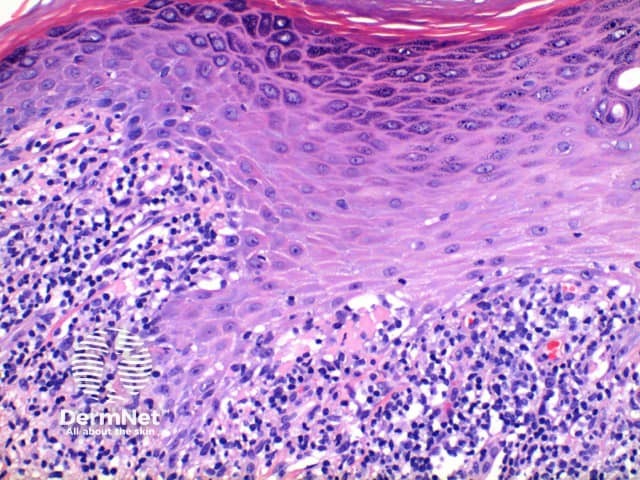

The histological features of lichen planus are:

Pathology of lichen planus